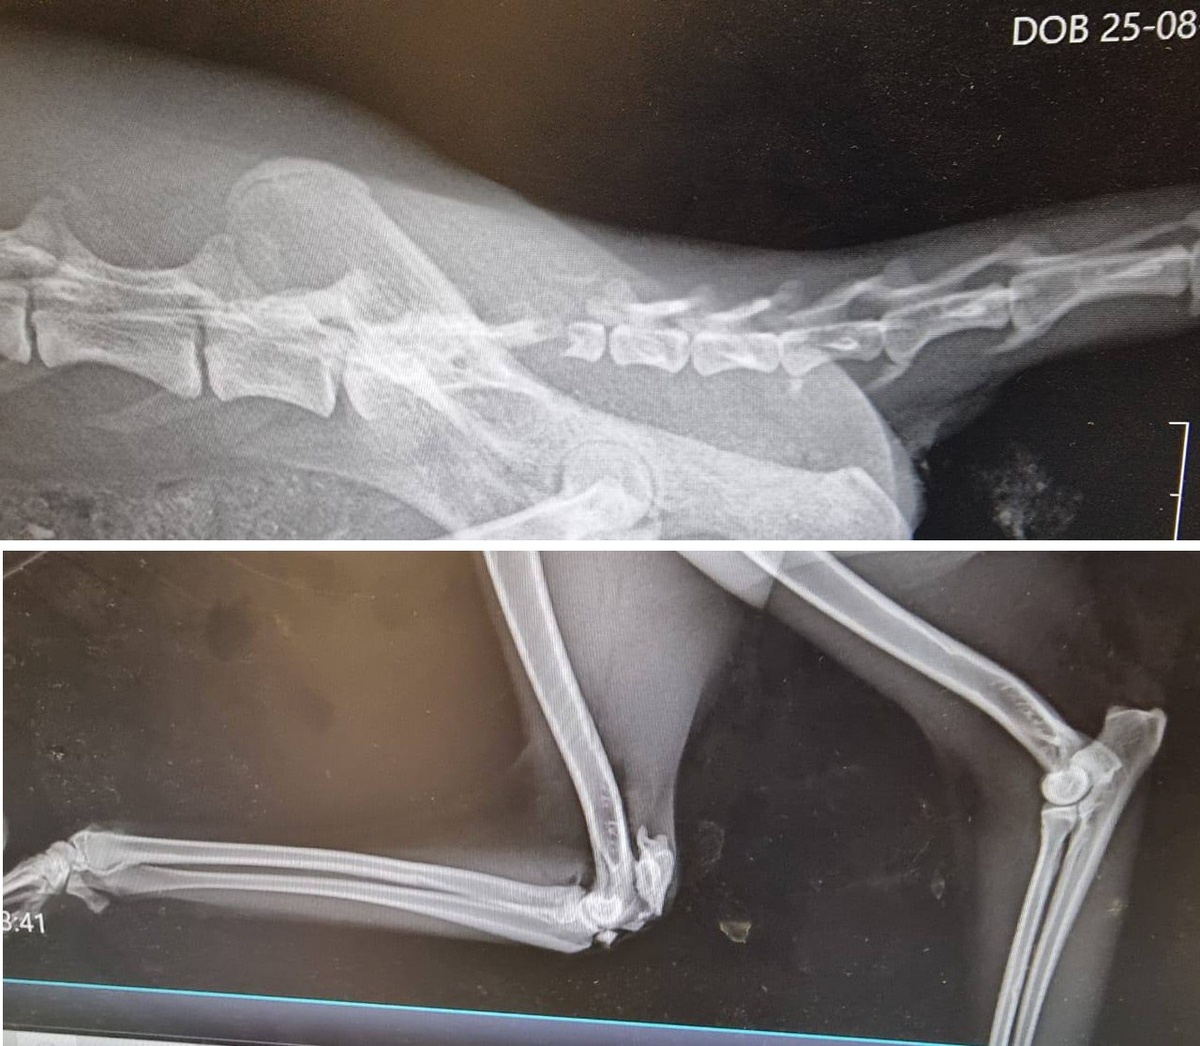

🐾 Зверя передали ветеринарам, а затем в специализированный центр реабилитации лис «Новолисье». Как сообщили специалисты центра, у лисёнка серьёзные травмы: перелом крестца и левой лапы со смещением, ушибы грудной клетки и позвоночника.

👩‍⚕️ Сейчас лис находится под наблюдением профессионалов. План лечения включает контроль за состоянием, а через несколько дней — операцию по удалению хвоста и остеосинтезу локтя.